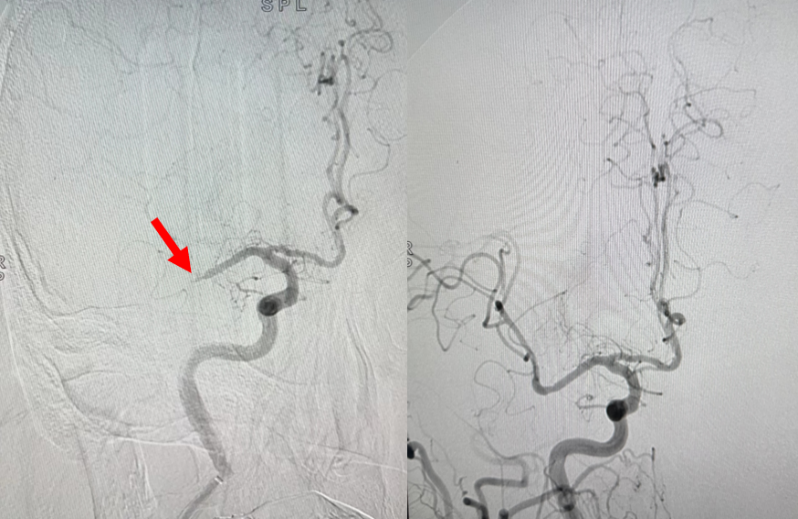

80岁的李大爷在家中突发左侧肢体不能活动,意识逐渐模糊。神经内科急诊值班医师接诊后快速启动卒中绿色通道,急诊行头颅CT排除脑出血,诊断为急性脑梗死,迅速进行溶栓治疗。在行颅脑CTA检查时,医生发现老人右侧大脑中动脉M1段远端闭塞。完善其他常规检查后,在麻醉科和介入室协助下,神经内科介入医师顺利施行右侧大脑中动脉栓塞取栓术,开通闭塞血管,转入NCU治疗。在NCU医护人员共同努力下,李大爷顺利度过了危险期,意识逐渐恢复,肢体活动及其他症状也有明显改善。

大脑中动脉闭塞取栓术